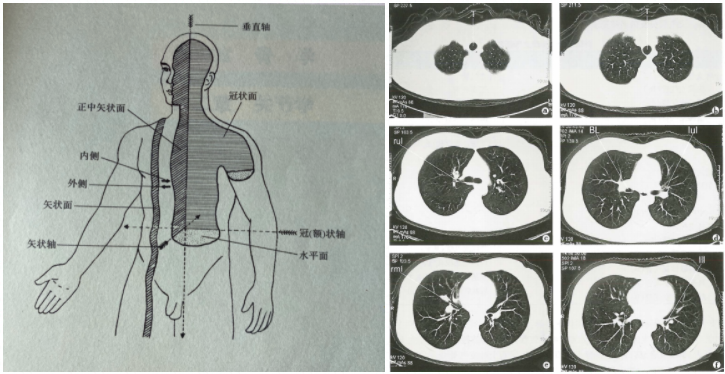

CT成像是比X射线更高分辨率的数字复制图像(特定于不同设备和处理技术的不同像素)。同时,CT成像的密度值是可量化的。高,中和低密度不仅可以用来描述图像,而且还可以直接描述密度的CT值。 CT通常使用水平轴断层扫描(即减半,法式面包的水平是什么水平),因此您通常会看到的CT膜总是一一偏椭圆形图像(右图如下图所示)。但是,在头部,脸部或颅骨CT检查期间,有时是冠状扫描(垂直分为两半的大型平面)是躺下并平坦的零件,以便每次都应该切割头部,剪切方向并清楚地看到。

图片的左侧显示了人体的轴和表面,图片来自Jilin Science和Technology Press Human Anatomy。图片的右侧显示了正常的肺窗口CT,该肺部CT与医学成像截获。

直接使用不同组织厚度和密度进行成像的CT称为CT扫描,通常可以在几分钟内完成检查。使用对比剂来帮助成像的CT称为CT增强。考试时间稍长。根据考试现场和增强技术,可能需要几分钟到半小时。随着CT技术的发展,“切片”的厚度越来越薄。应用螺旋CT后,可以将成像视为连续且均匀的扫描。在患者检查后,可以取出存储的膜并选择某个部分进行打印。在使用最新成像系统的医院中,医生可以直接观察到计算机上成像系统中患者的CT扫描的每个级别,如果需要进一步操作,将进行进一步的操作。图像处理也可以在原始扫描图像上进行,而无需患者进行次要检查。